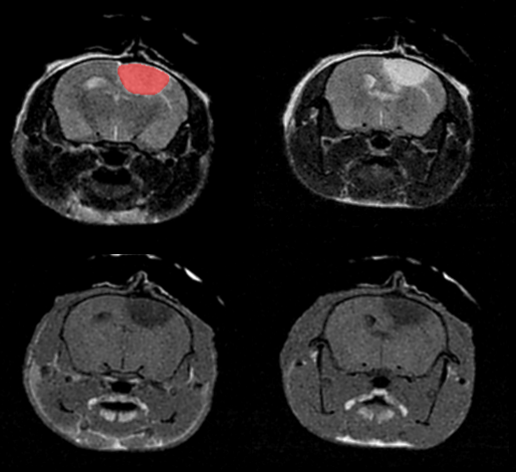

Tumor visualization in various cancer models: Fat-suppressed T2-weighted imaging can be used to detect and quantitatively characterize the growth of a wide range of cancer models. Image Credit: Scintica Instrumentation Inc

Fat-suppressed T2-weighted imaging can be used to detect and quantitatively characterize the growth of a wide range of cancer models. Image Credit: Scintica Instrumentation Inc

Monitoring tumor growth in the mouse brain, following the orthotopic injection of glioblastoma cells, using T2-weighted images. Image Credit: Scintica Instrumentation Inc